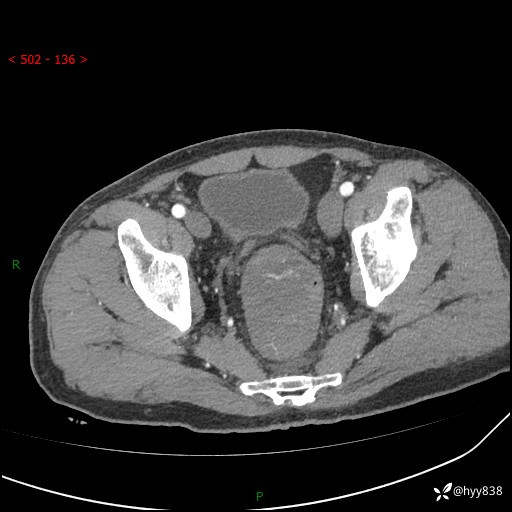

盆腔CT平扫+增强